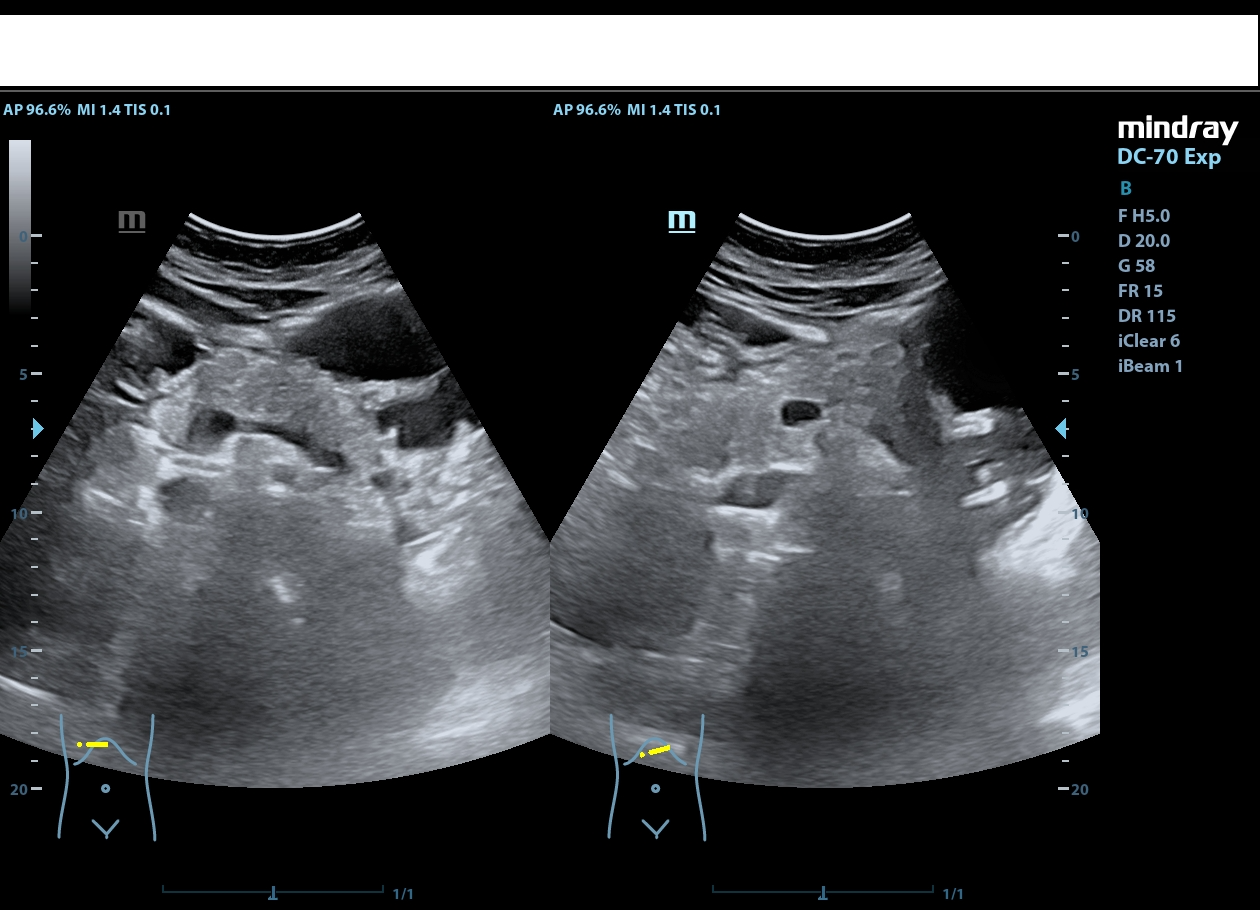

Riñón derecho de ecoestructura conservada, con dilatación pielocalicial grado I. Riñón izquierdo con adelgazamiento cortical y ureterohidronefrosis grado IV, sin poder localizarse el origen de la obstrucción, ausencia de jet ureteral izquierdo. Hallazgos sugestivos de síndrome de la unión pieloureteral.

Su diagnóstico se realiza mediante ecografía para valorar la hidronefrosis y se confirma mediante UroTAC, para evaluar la obstrucción.